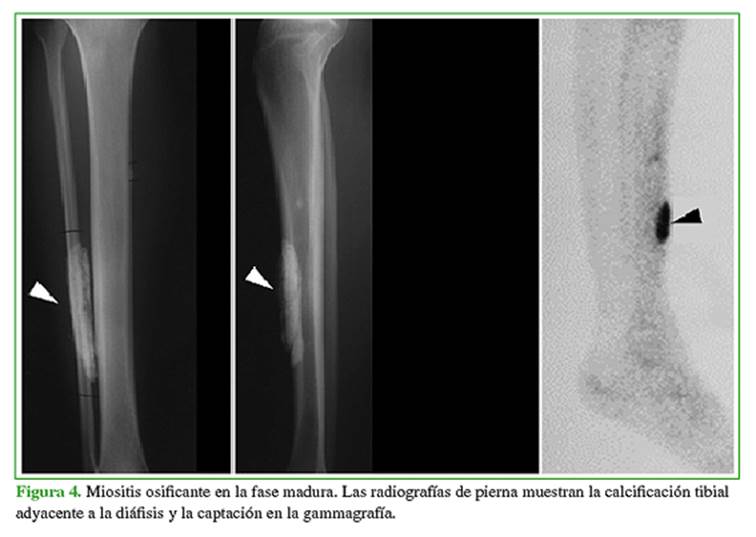

Miositis osificante circunscrita: se refiere a hueso nuevo que suele aparecer después de un traumatismo (Figuras 4 y 5).

El aspecto radiográfico típico de la miositis osificante es una calcificación circunferencial con un centro brillante y una hendidura radiolúcida que separa la lesión de la corteza del hueso adyacente. En la radiografía convencional, inicialmente, no hay calcificación, pero puede haber inflamación de los tejidos blandos. La calcificación suele manifestarse en un plazo de 2 a 6 semanas y la lesión alcanza el aspecto clásico de calcificación periférica bien circunscrita a los dos meses. Durante los siguientes cuatro meses aproximadamente, por lo general, las calcificaciones se vuelven más pequeñas y densas. La hendidura radiolúcida puede ser difícil de observar en las radiografías convencionales.

En las primeras etapas del desarrollo de la lesión, se observa la captación aumentada inespecífica de la gammagrafía ósea que disminuye gradualmente a medida que la lesión madura.